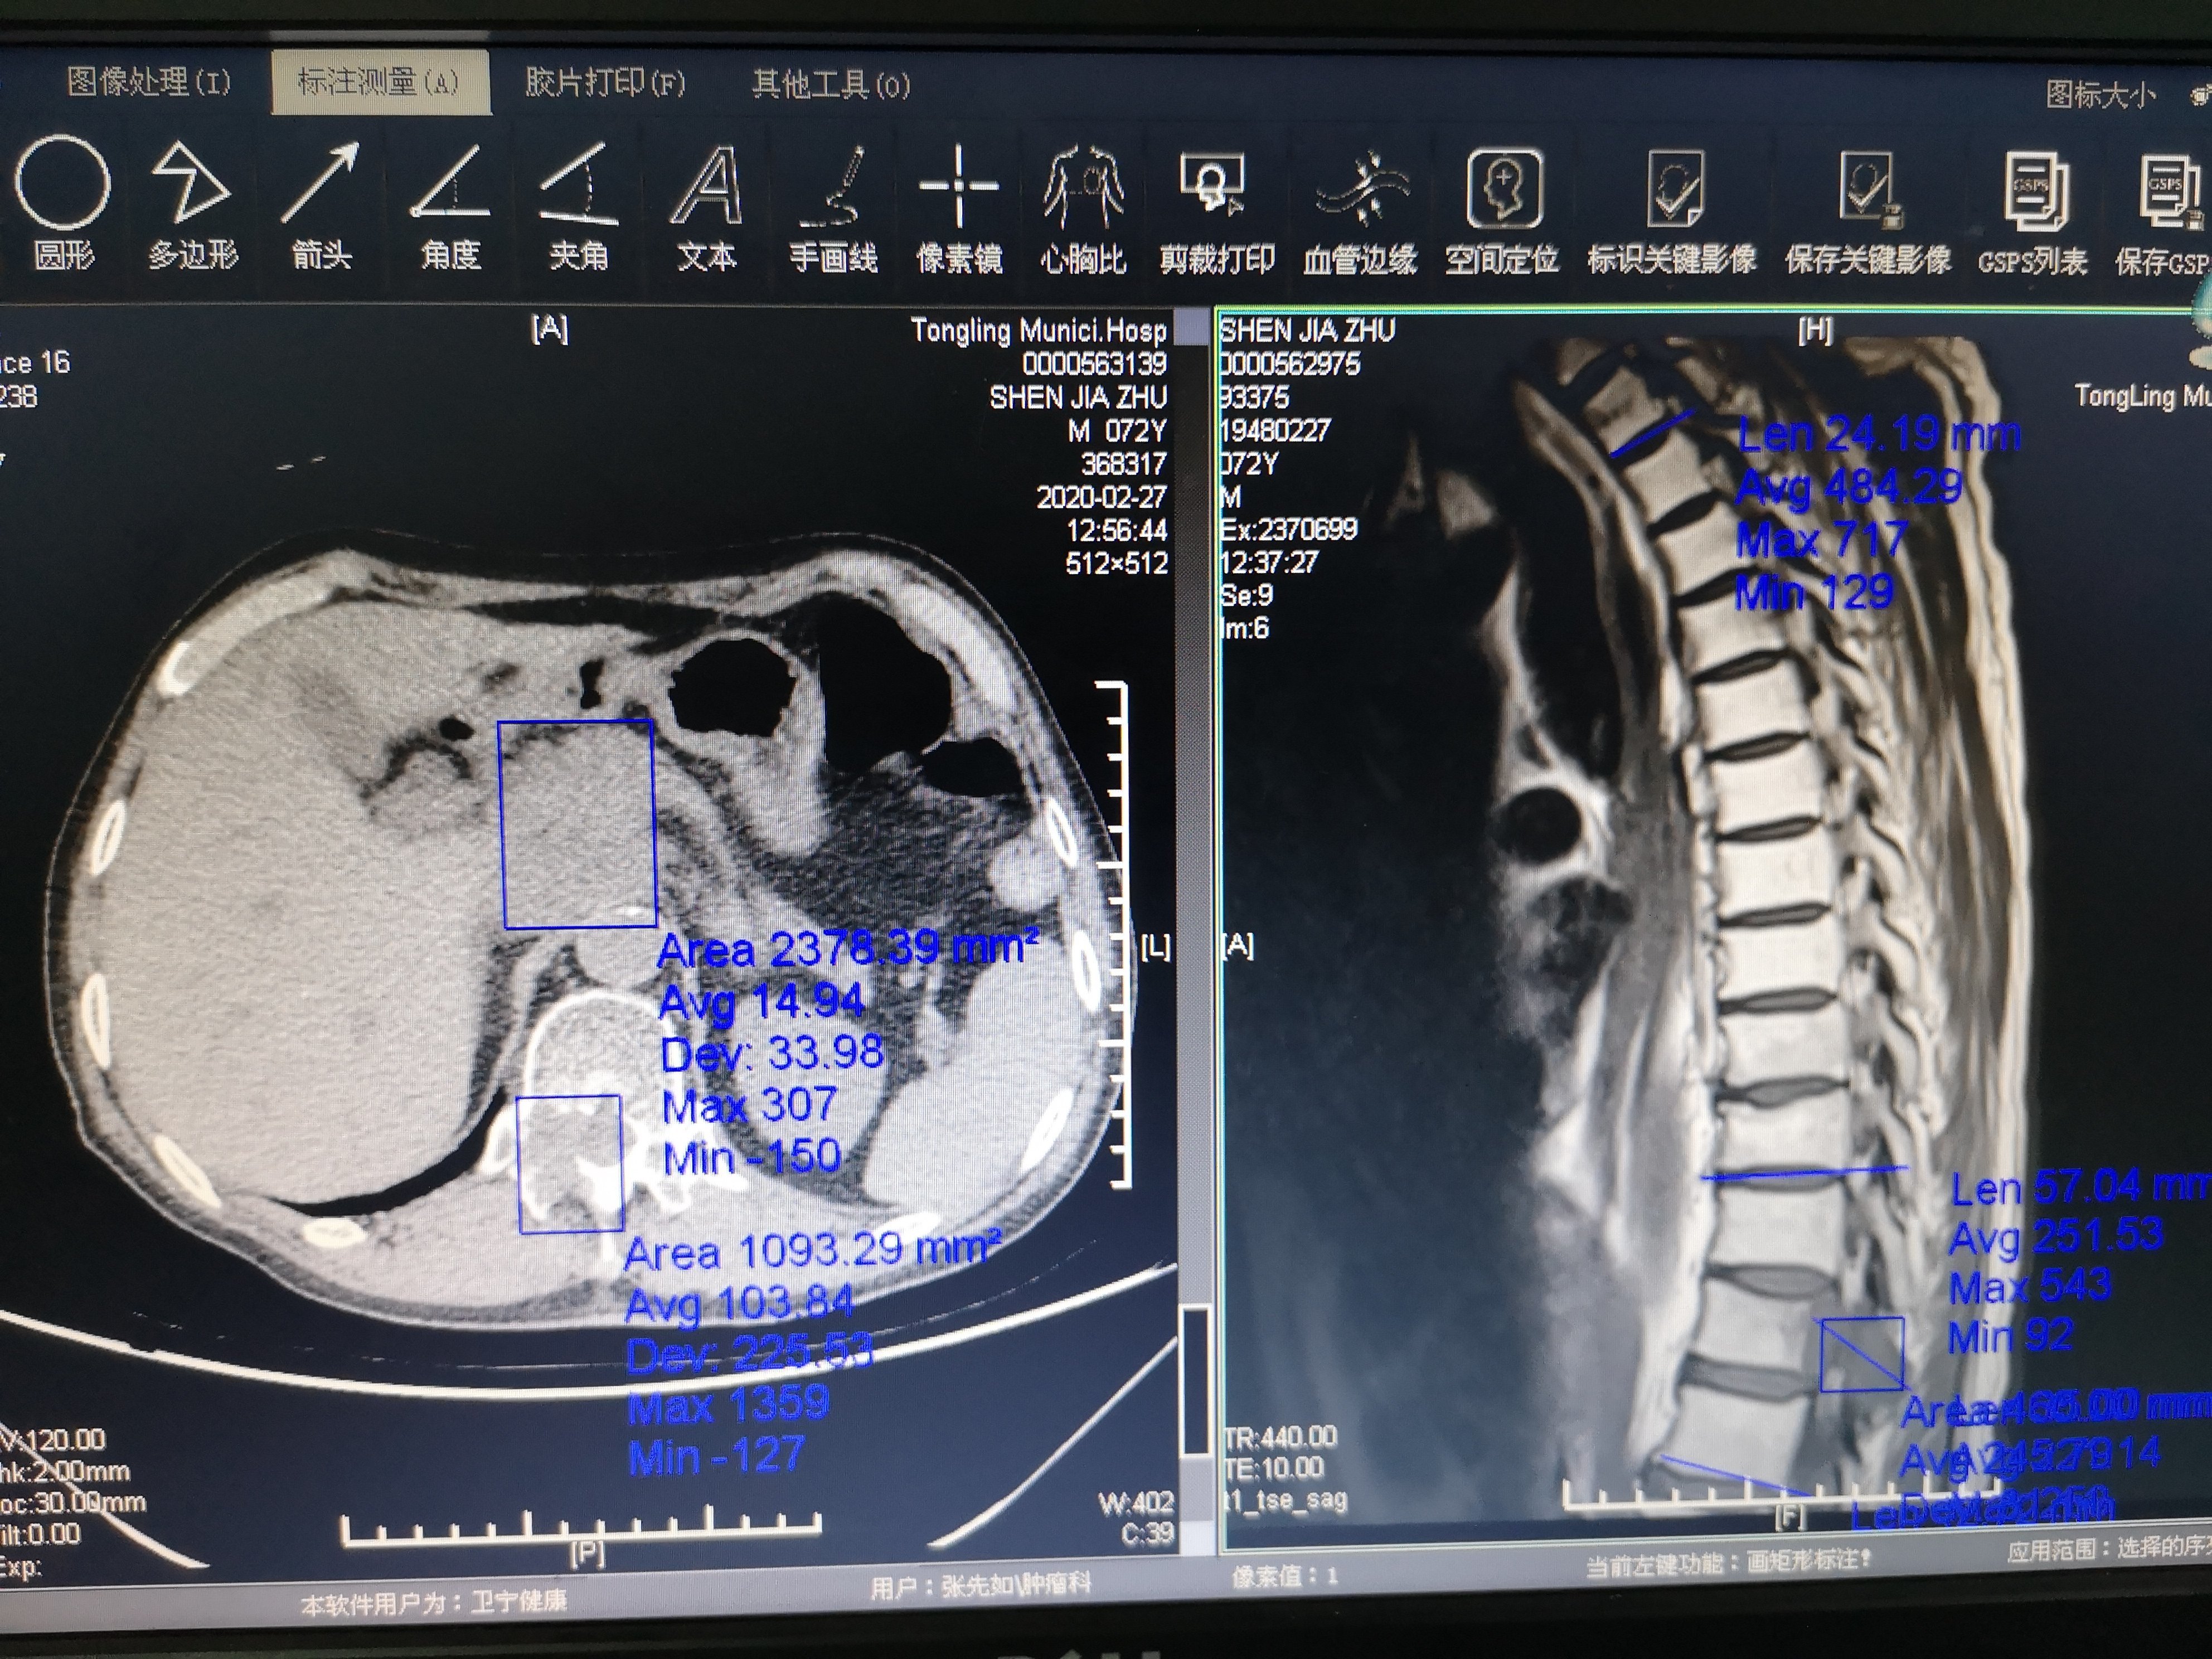

然后这一次这个病号来到我们医院给他做了一个磁共振和CT我们来看下图

从上面这张CT图我们可以看出这个患者左侧有胸腔积液,就是我上面标注的地方。这说明他的肺已经转移了!

再往下看看到他腹膜后胰头处淋巴结融合团块,就是我上面标注的地方,这说明他的腹腔淋巴结也转移了!好,我们继续往下看!

从这张图上看我们可以看到左侧上面的方框内是腹腔转移,下面的小方框就是我刚才看到的椎体转移CT片,也就是右边骨转移磁共振的对应位置!